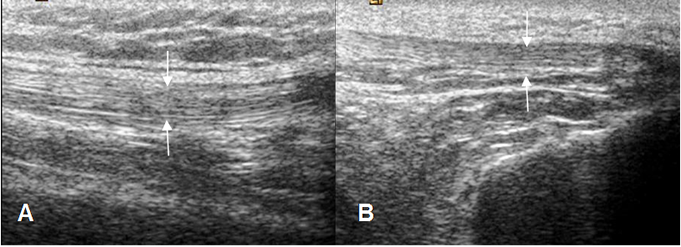

El mecanismo extensor es de fácil evaluación debido a su localización superficial. Los músculos cuadriceps y el tendón patelar muestran una ecotextura fibrilar y paralela. El tendón del cuadriceps puede ser hipoecoico en su inserción patelar, por la anisotropía y no debe ser confundido con patología. (9). (Fig 9).

Fig 9. Mecanismo extensor.

A y B: Ecografía sagital. Tendones normales del cuadriceps en A y patelar en B (Flechas).